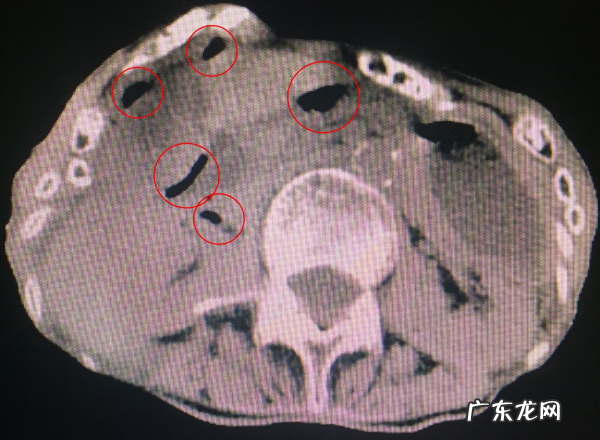

患者中年男性,未婚,平时与母亲生活在一起,来院时腹痛已经4天了,急诊同事进行常规检查后发现,患者全腹都有压痛和反跳痛(反跳痛是腹膜刺激征的表现,提示炎症已经波及全腹),白细胞27×10^9/L(白细胞正常值是4.0-10.0×10^9/L),于是紧接着给患者进行了腹部CT检查,果不其然,消化道穿孔(图1) 。

图1 腹部CT 圆圈显示腹腔游离气体影,是消化道穿孔的特异性表现